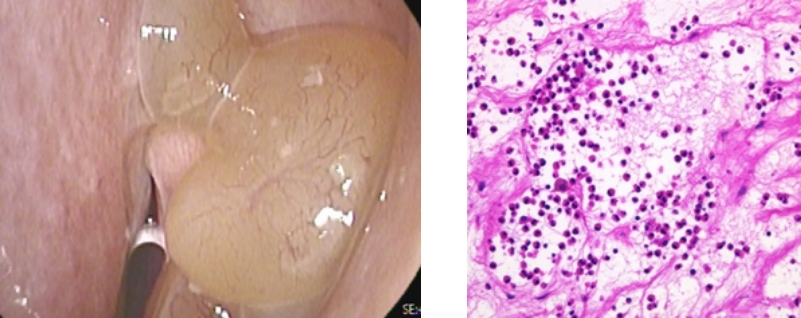

左図は好酸球性副鼻腔炎の患者さんの内視鏡写真です。水ぶくれのような袋が鼻茸であり、幾つもの鼻茸ができて鼻の中を充満していくのが特徴です。

右図は好酸球性副鼻腔炎の患者さんの鼻茸の顕微鏡写真です。核が青紫色に染まった好酸球が多数確認できます。